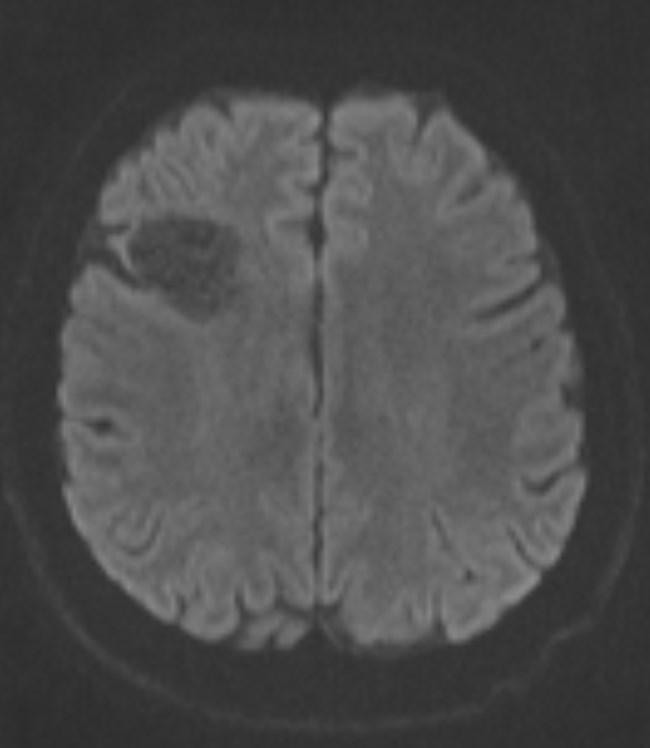

Answer: Primary hydatid cyst of right frontal lobe.

MR images revealed Gharbi type V hydatid cysts in right frontal lobe.

Gharbi classified hydatid cyst ultrasonographic images into 5 types: Type 1, walled, unilocular, anechoic; type 2, separated membranes; type 3, multisepta, daughter vesicles; type 4, heterogenic, hypo-hyperechogenic; type 5, calcification of a section of the wall or completely calcified (4). The cysts characteristically have three components: Pericyst, Exocyst, and Endocyst.